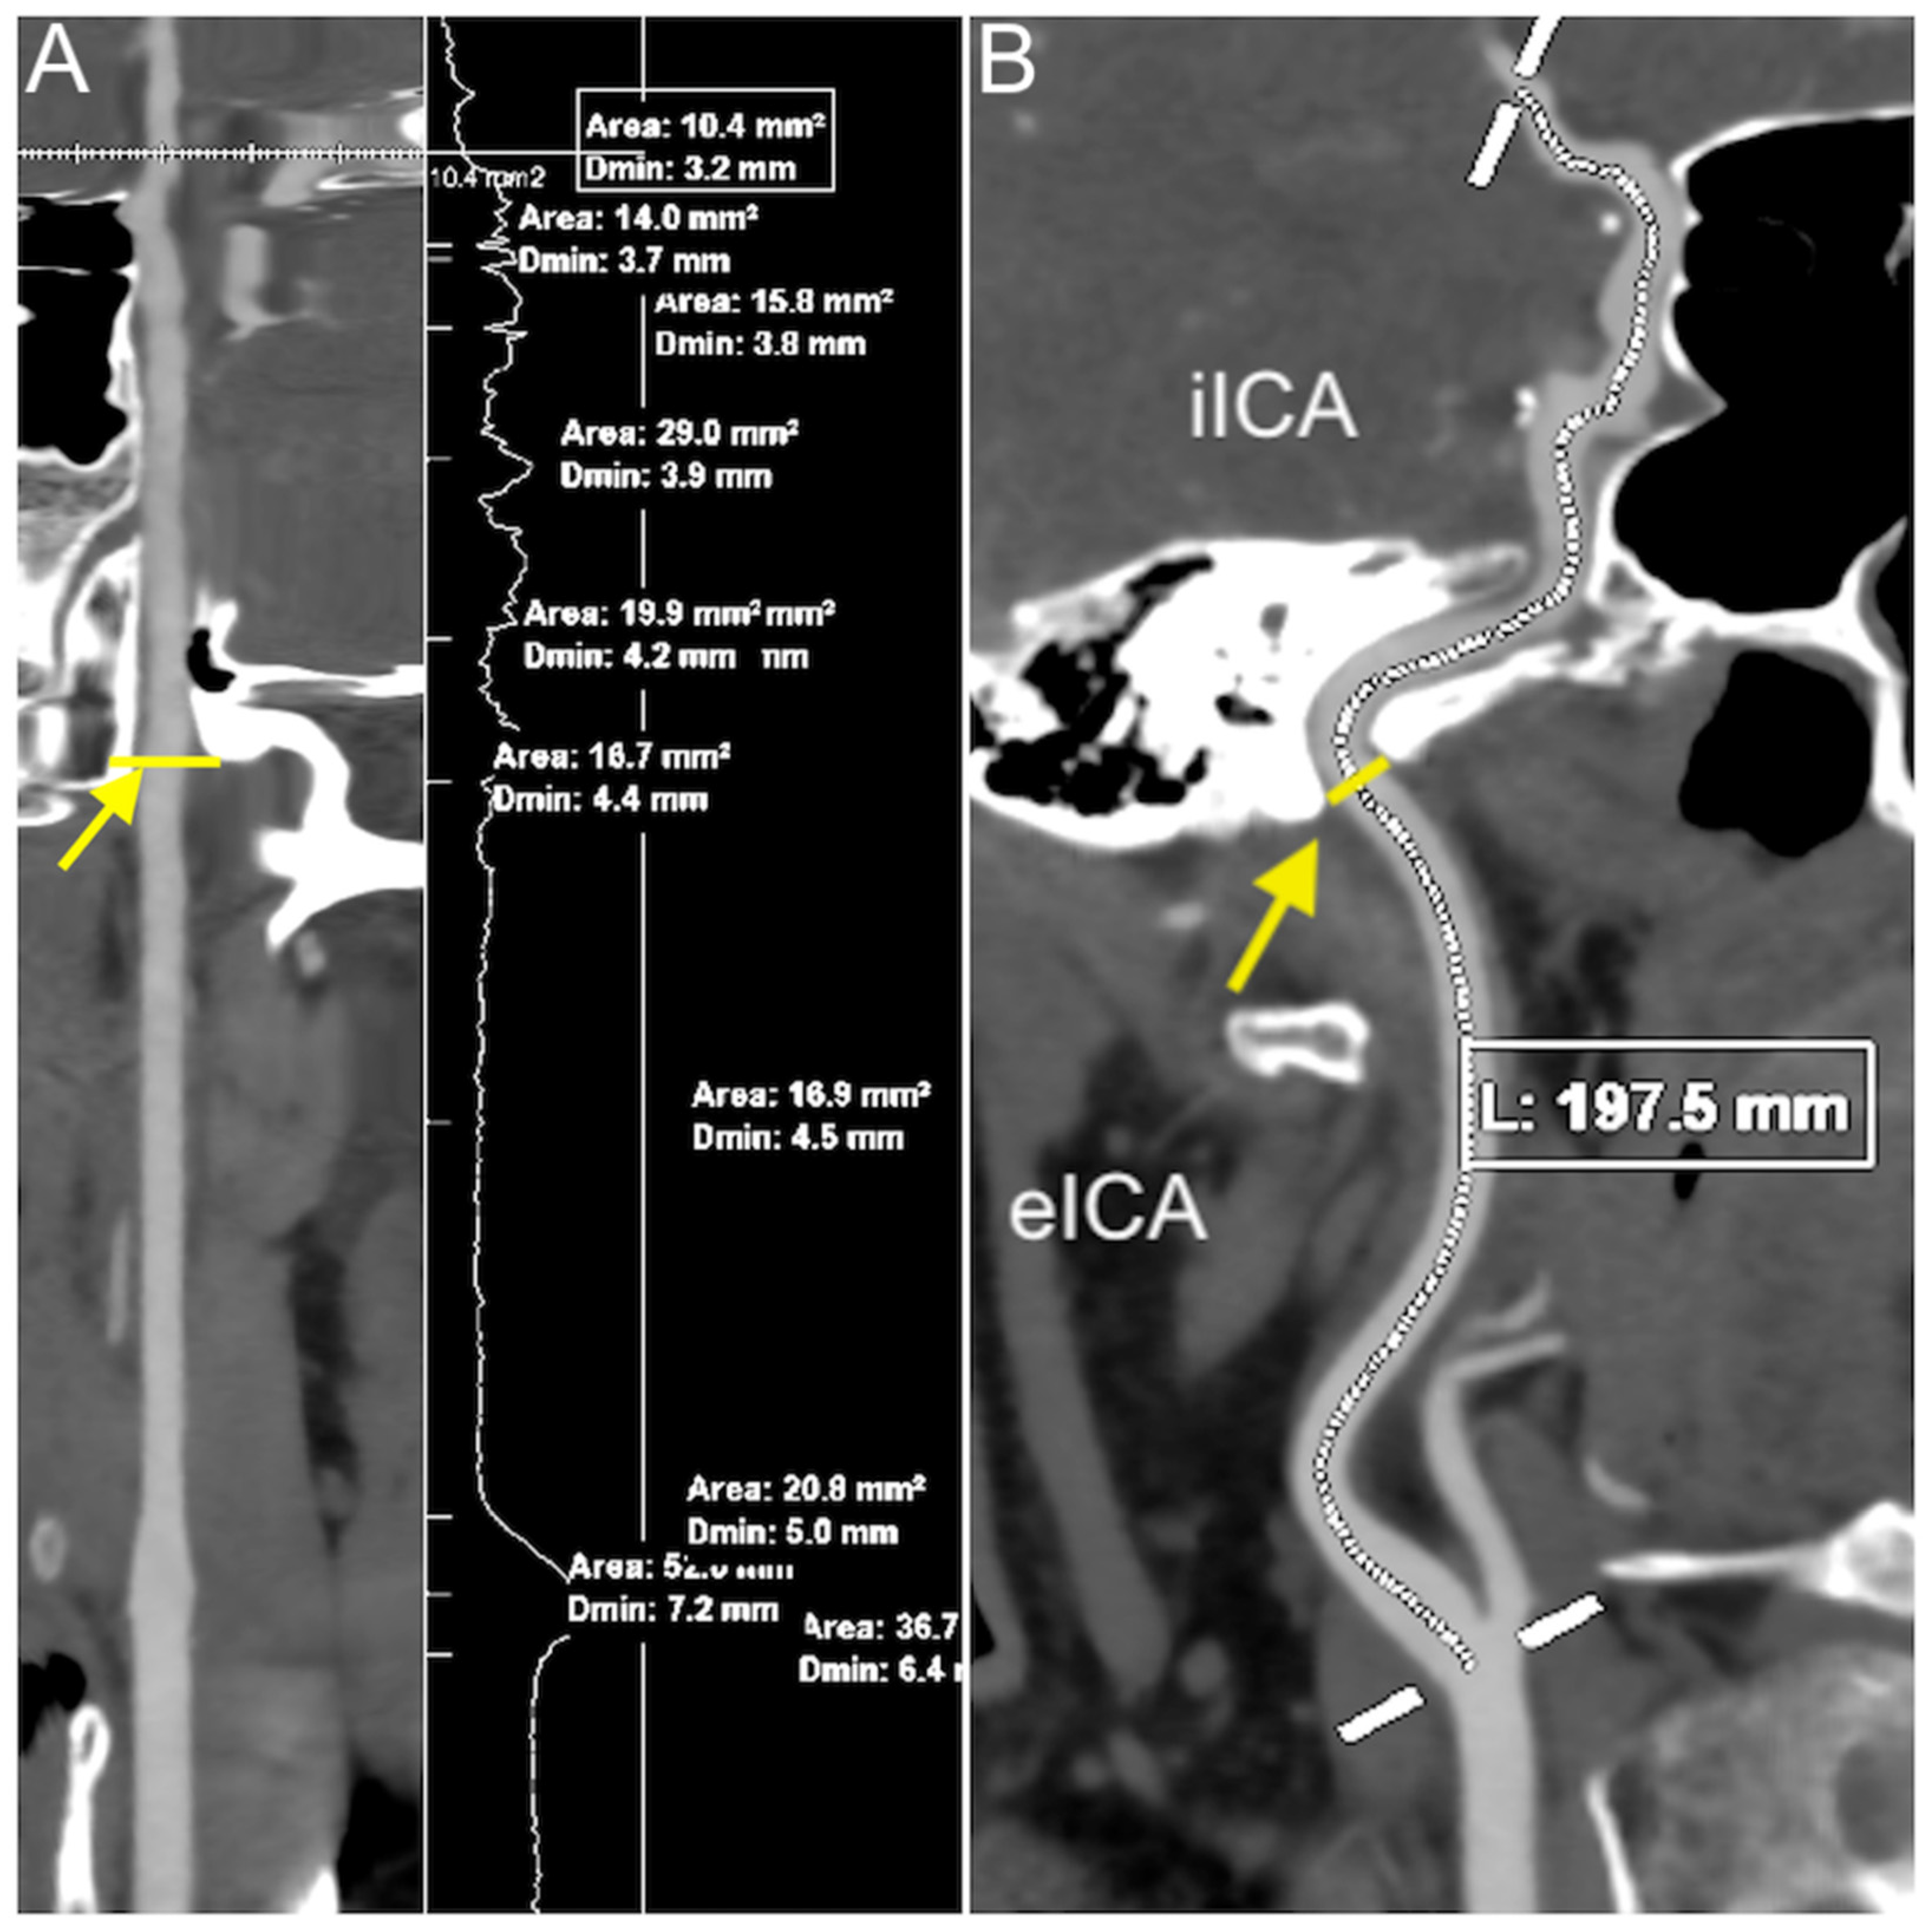

| Total ICA length | 154.89 (±26.17) | 155.20 (±23.57) | 0.7895 | 160.62 (±28.56) | 150.07 (±19.83) | 0.0141 |

| Extracranial length | 86.10 (±18.65) | p < 0.0001 | p = 0.0052 | p = 0.0197 |

| Intracranial length | 69.36 (±8.69) | p < 0.0001 | p < 0.0001 | p < 0.0001 |

| Total ICA length | 155.04 (±24.90) | p < 0.0001 | p < 0.0001 | p = 0.0004 |